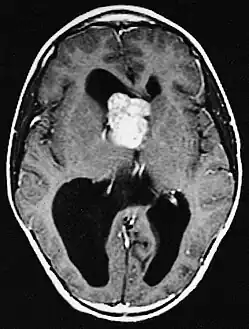

a,b)Images of subependymal giant cell astrocytomas arrowheads

MRI of brain with sub-ependymal giant cell astrocytoma

Diagnosis is made by imaging with a contrast-enhanced MRI or CT scan of the brain.[3]